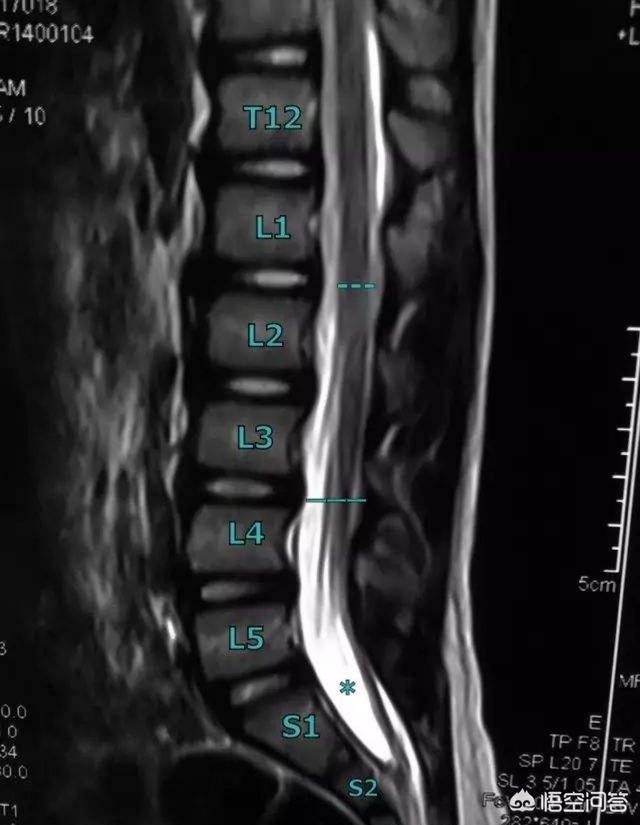

还有,有的人先天椎管直径很小,有的人则很大,这就表示,同样的中央型突出,在不同人身上,一定有各自特点(当然,也不是椎管直径大的一定症状轻),一定记住,影像学检查的突出大小和方向,仅供参考,不是一个准确的诊断!

临床中,我遇到超过8mm巨大中央型突出近百例,基本都保守效果很好,有的是一侧症状,有的是双侧,后者的恢复难度略大于前者,其他类型的更多,实际上腰椎间盘突出症多数还是发生在侧椎管,也就是一侧腰痛和腿痛的居多,同时一定要排除腰臀肌劳损造成的症状,减少误诊几率!

严不严重需要看突出的间盘,突出程度,突出部位。还有椎体后关节的稳定程度。如果在神经根发出的肩部、神经根出椎间孔的部位或者侧隐窝突出,神经根受压就很严重。如果不是上述部位,而且是腰五骶一这种神经根走行比较长的、椎体后关节稳定的,就不算严重,经过适当的非手术疗法可以稳定病情,免除手术。但是如果出现鞍区麻木就非常严重了,必须马上!立刻!手术!解除压迫。不然终身大小便都不受控制,更不说生殖功能了。